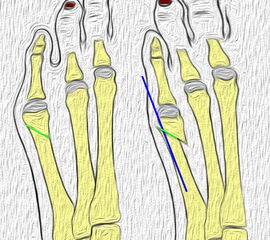

Röntgenmorphologische Einteilung nach Coughlin (I-III) ergänzt durch Fallat (IV) (Arnold 2002) 34

Typ I: Vergrößerter Metatarsale V Kopf

Typ II: Laterale Seitausbiegung des distalen Os metatarsale V

Typ III: Vergrößerter Intermetatarsalwinkel IV/V von mehr als 8°

Typ IV: Kombination von mindestens 2 Typen I-III

Abb. 2: Tailors bunion Typ I bis III (nach Coughlin)